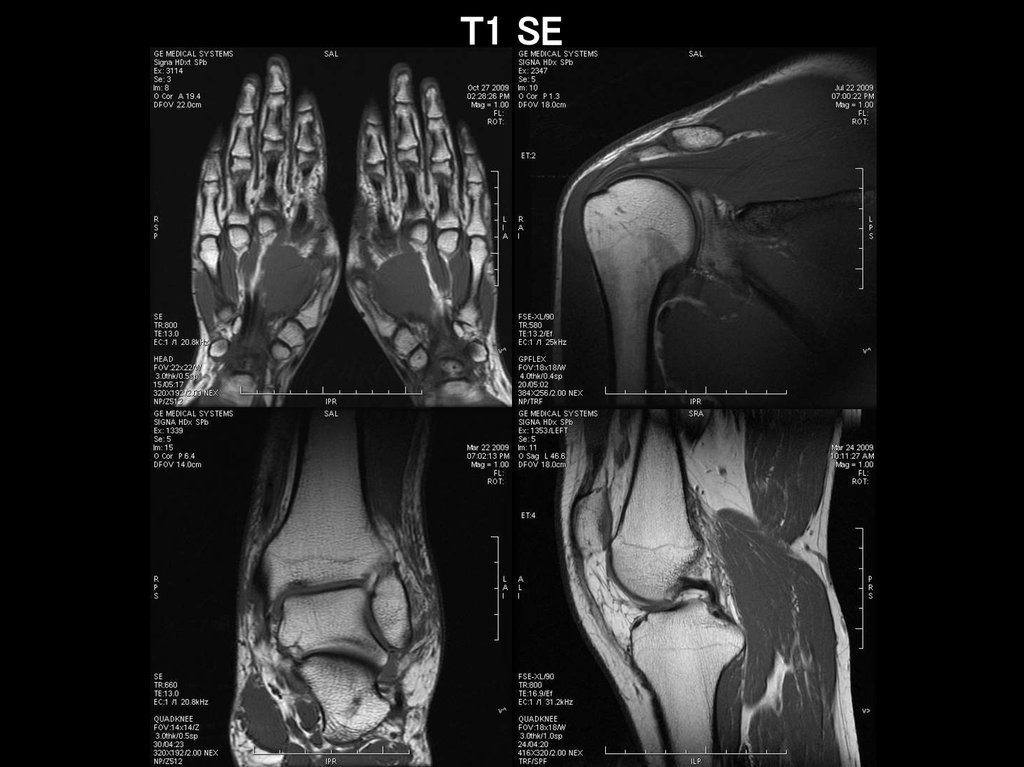

T1 SE